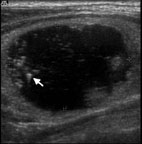

楊小姐因為頸部酸痛到耳鼻喉科門診求診,頭頸部的局部檢查並沒有明顯異常,頭頸部超音波檢查發現右側甲狀腺結節(圖9),低超音波影像發現是實心的腫瘤且有微小鈣化,超音波導引下細針穿刺細胞學檢查發現甲狀腺偶發瘤裡面的甲狀腺癌。病患接受甲狀腺切除手術,發現只有一個一公分不到的甲狀腺微小癌 (Microcarcinoma of thyroid) (圖10)。甲狀腺微小癌是指小於1公分的微小甲狀腺癌,大部分的甲狀腺偶發瘤裡面的甲狀腺癌大小會小於1公分,所以也會是甲狀腺微小癌,頭頸部超音波檢查可以用來及早診斷甲狀腺微小癌,甚至 2mm 的甲狀腺微小癌都有可能被超音波發現。

圖9. 楊小姐因為頸部酸痛到耳鼻喉科門診求診,頭頸部的局部檢查並沒有明顯異常,頭頸部超音波檢查發現右側甲狀腺結節,超音波影像發現是實心的腫瘤且有微小鈣化(箭頭所指處),超音波導引下細針穿刺細胞學檢查發現甲狀腺乳突。

圖10. 楊小姐接受甲狀腺切除手術,發現只有一個一公分不到的甲狀腺微小乳突癌(箭頭所指處)